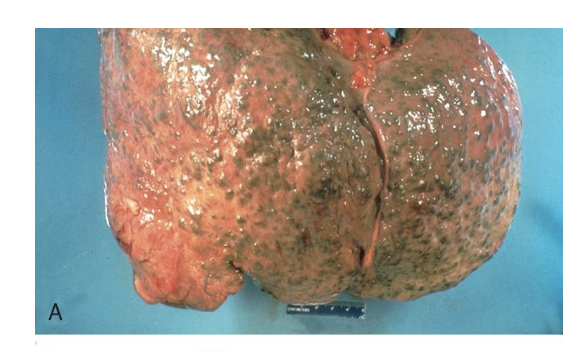

What liver pathology is seen here?

Cirrhosis that leads to obstruction of biliary secretion from liver so there is green nodules on liver due to build up of bile in liver